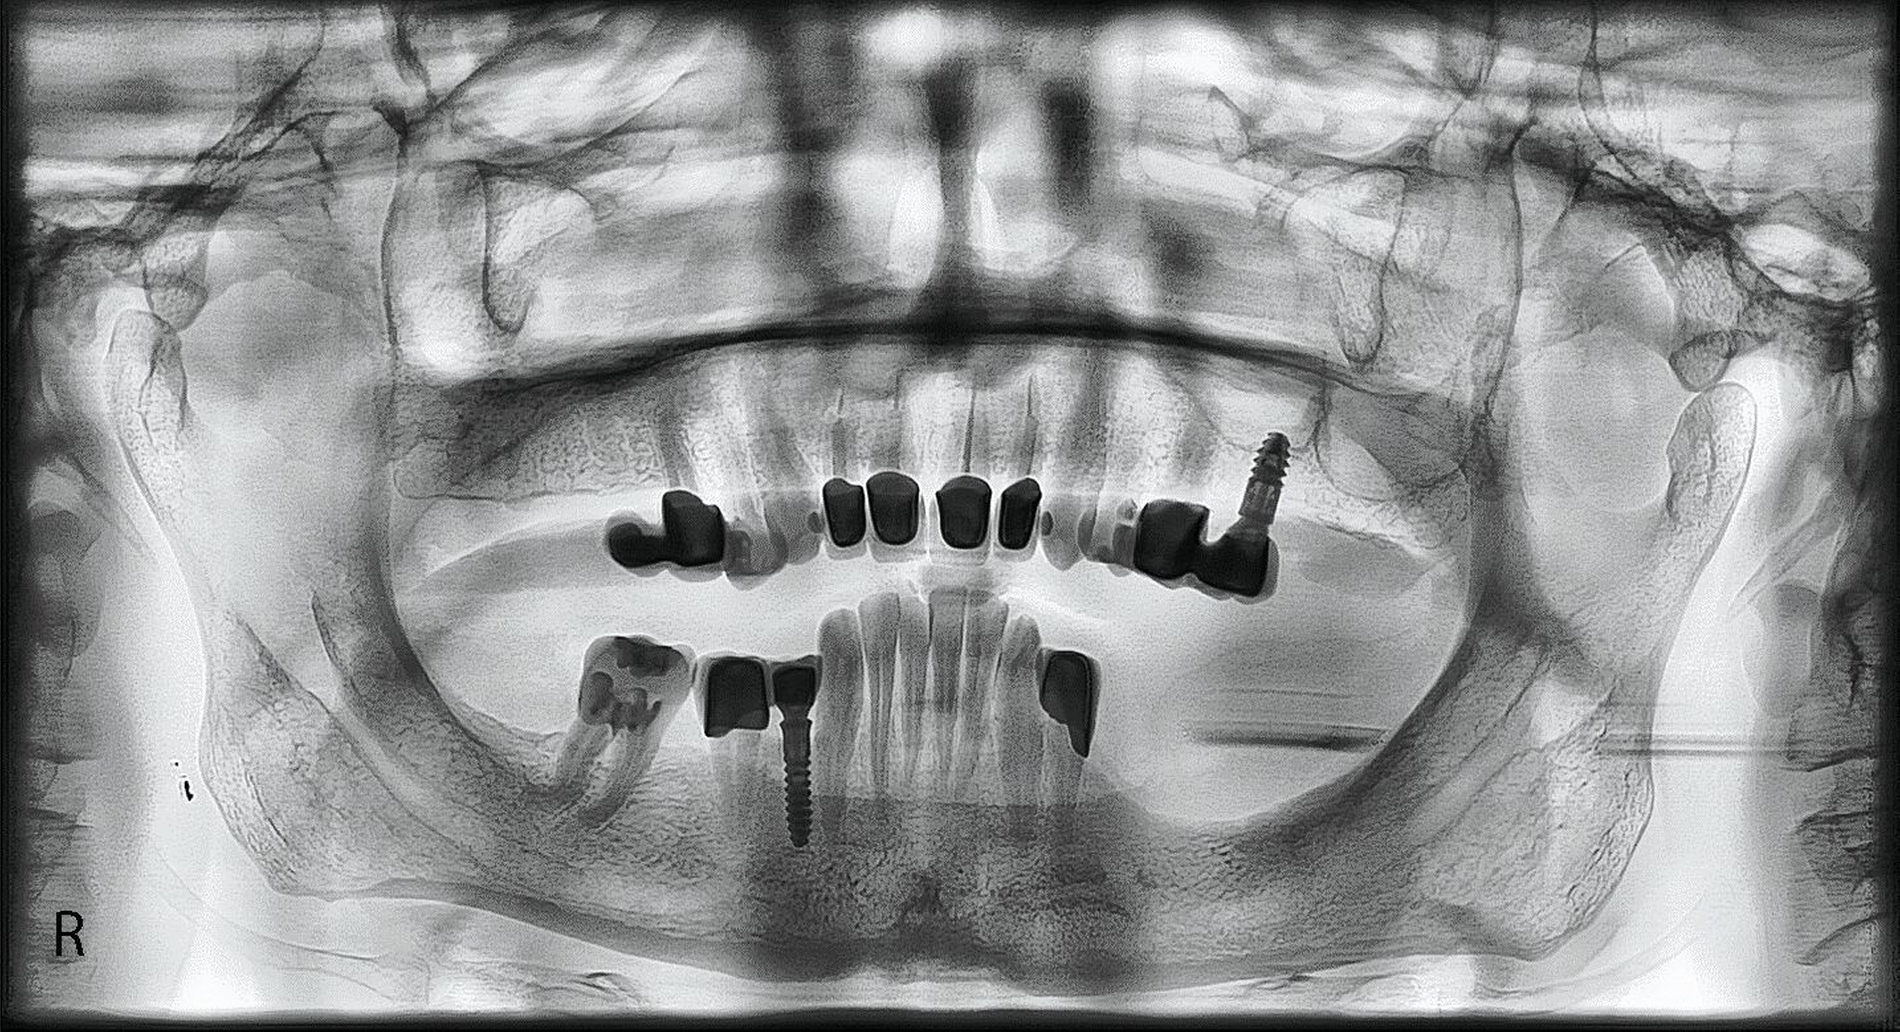

Radiologische Befundung

Auf der Panoramaschichtaufnahme sind aus funktioneller Sicht vor allem die Kiefergelenke und die Kieferwinkel von besonderem Interesse [Türp et al., 2016; Türp et al., 2021; Simonek et al., 2024]: Die mit langjährigem Kieferpressen einhergehenden funktionellen Belastungen (hohe Beißkräfte bei lang anhaltender Kontraktion der Kieferschließer) können zu knöchernen Anpassungen führen, die als biologische Remodellierung zu interpretieren sind. Diese äußern sich auf der Panoramaschichtaufnahme in folgenden Befunden:

Kondylus beziehungsweise Tuberculum articulare: Knochenresorption (glatte Abflachung); Grund: Druckbelastung im Bereich der artikulierenden Flächen des Kiefergelenks (Abbildung 1),

Kieferwinkelbereich: Knochenapposition; Grund: Zugbelastung durch die dort ansetzenden Sehnen des M. masseter und des M. pterygoideus medialis (Abbildungen 1 und 2).

Ferner lässt das Röntgenbild einen Eindruck über den Grad der Attrition beziehungsweise Abrasion der Zähne zu, aber diese Einschätzung lässt sich klinisch genauer vornehmen.